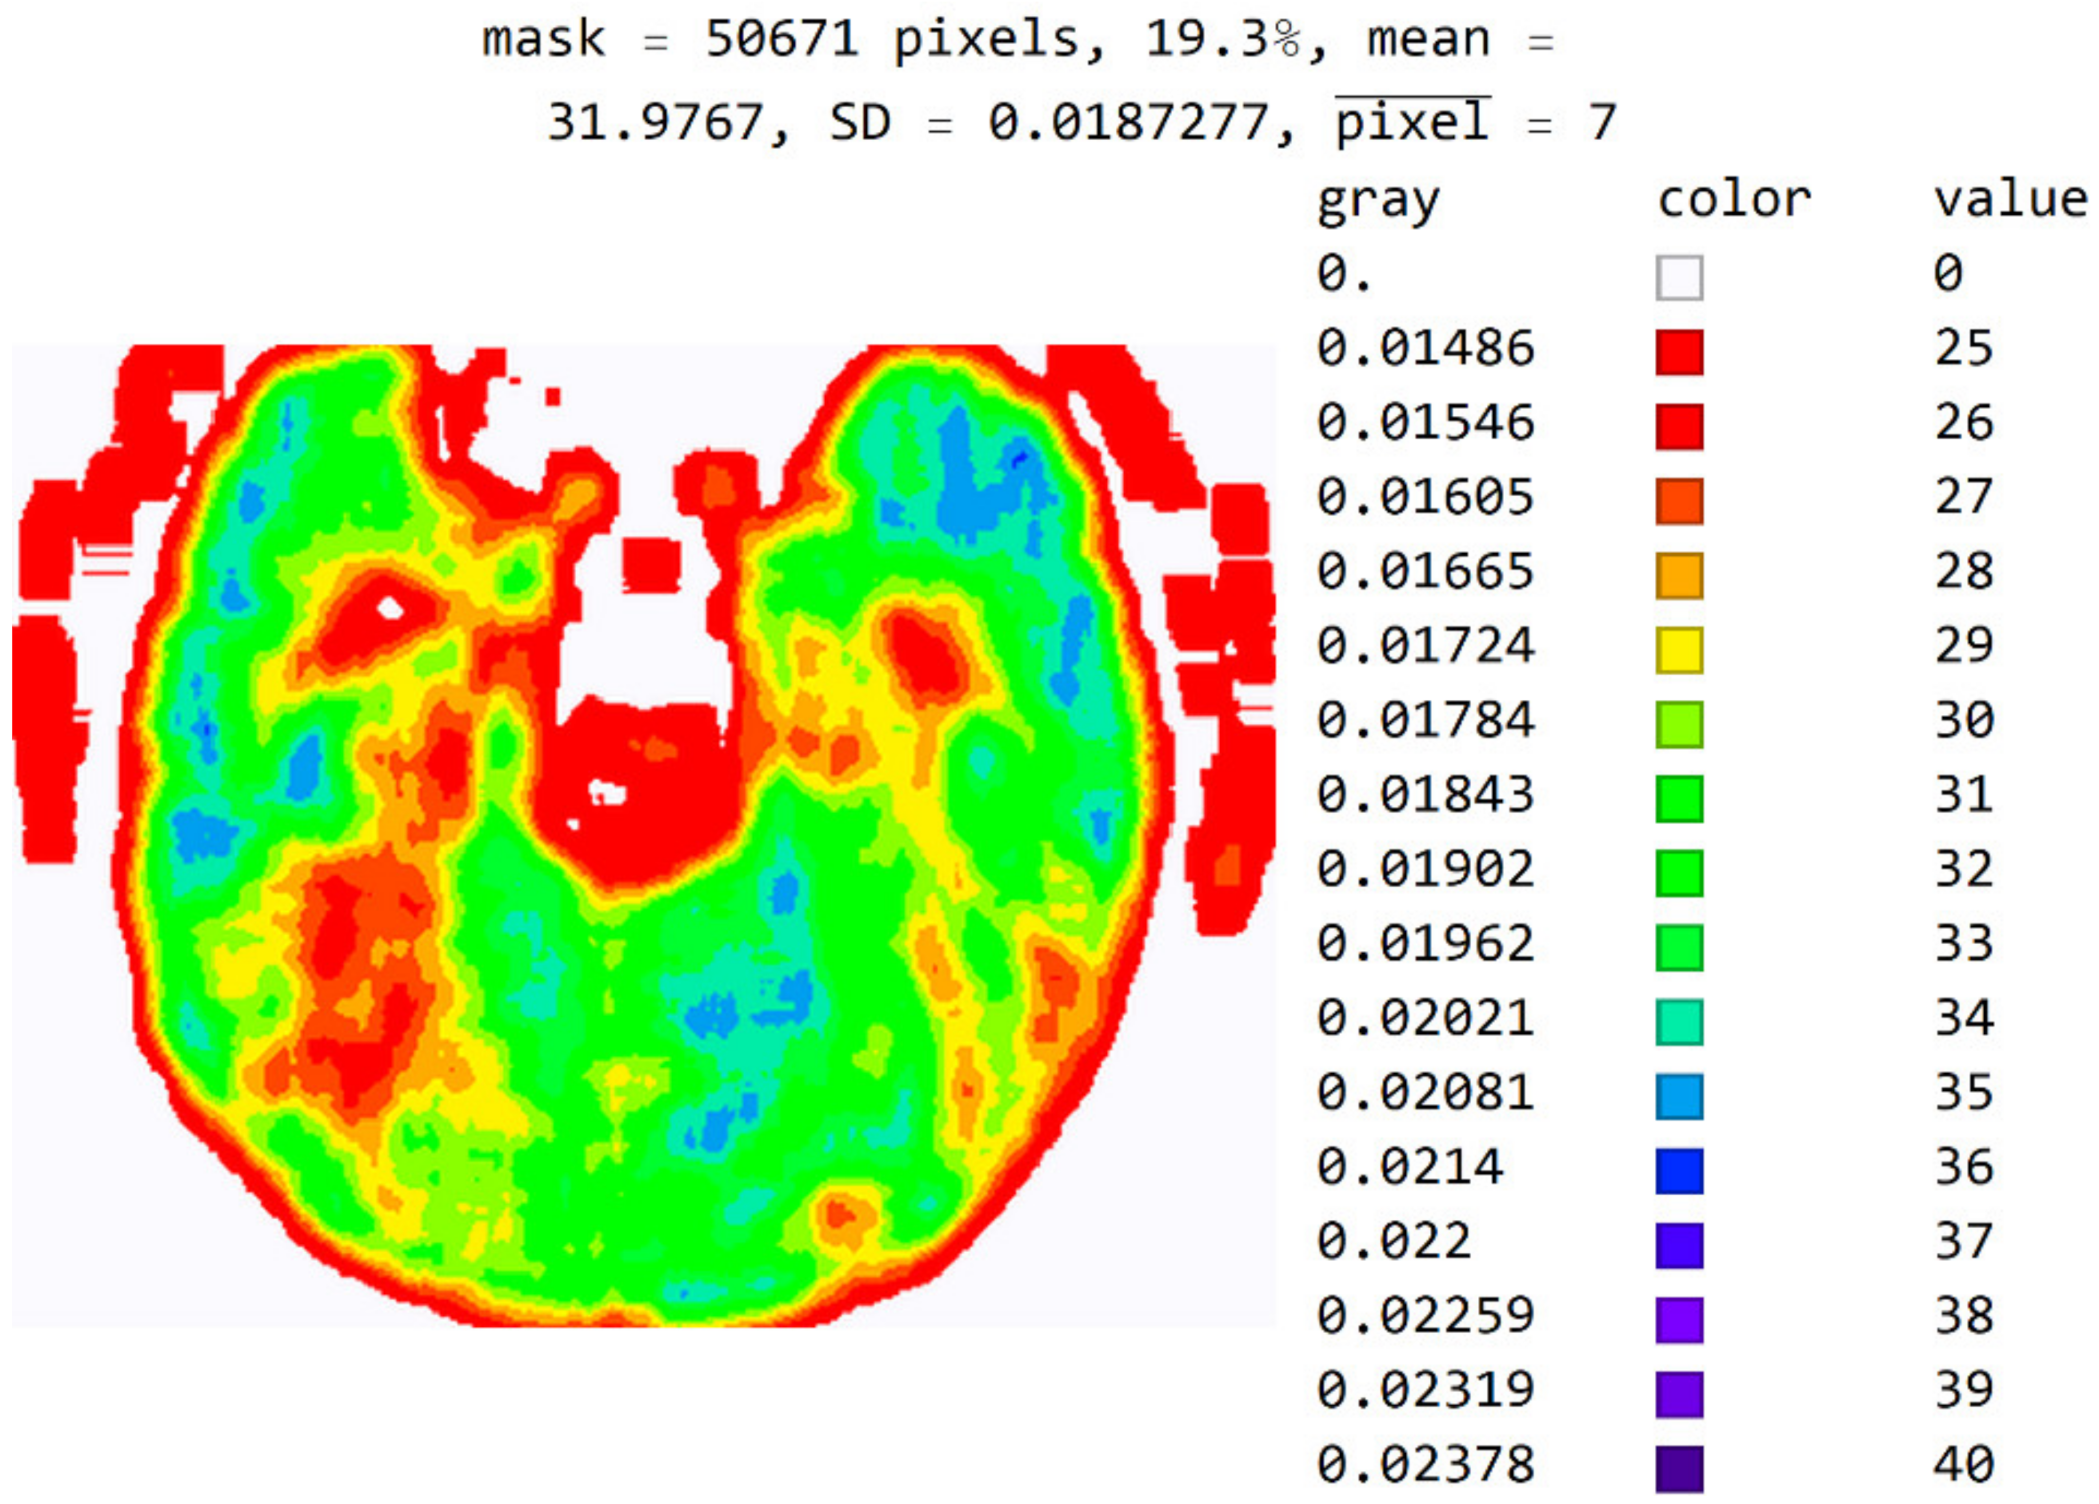

2.2. Smart Visualization Method (SVMI)

3.1. Technological Description